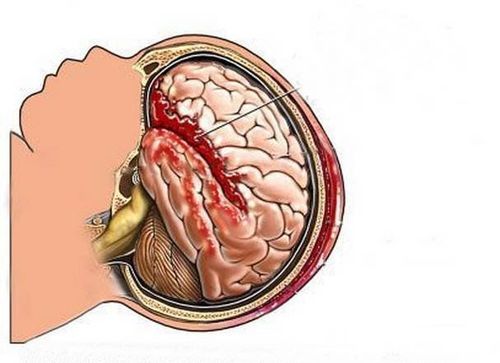

2.2 Chảy máu

Một vết bầm tím của mô não thường kết hợp với sưng (phù nề) và tăng áp lực trong hộp sọ, được gọi là áp lực nội sọ (ICP). Các triệu chứng của tăng áp lực trong não và hộp sọ bao gồm: đồng tử giãn ra, huyết áp cao, nhịp tim thấp và nhịp thở bất thường.

Nghiêm trọng hơn, chấn thương sọ não sẽ yêu cầu chăm sóc cấp cứu cá nhân và thường xuyên, chẳng hạn như phẫu thuật để loại bỏ cục máu đông và giảm áp lực lên não.